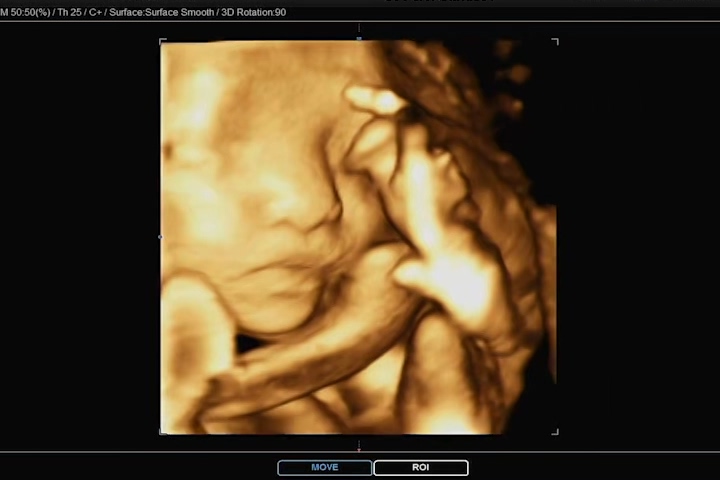

우리 까꿍에 엄마 뱃속의 태반에 머리를 기대고 한쪽 손을 올리고 있어 깔끔하게 얼굴을 보지 못했지만, 나름 만족하게 얼굴을 볼 수 있었다. 사실 이번 초음파 사진 정도까지도 기대하지 않고, 코와 입술 살짝만 나왔으면 좋겠다 했건만 그 이상의 모습도 보여줬다.

잠을 자고 있는지 평소에 비해 움직임이 없던 까꿍이. 보통 3D 초음파는 눈을 감고 있기 때문에 눈 부분은 디테일하게 나오지 않는다고 하셨다. 그래도 영상 중간중간과 초음파 사진에는 눈 윤곽도 나와있어서 얼굴의 형태를 느낄 수 있었다.

심박수와 손, 발 다섯개씩 무사히 잘 있고, 척추도 올곧게 있고 다행이다. 요 며칠 새 아내의 배를 만질 때 태동을 몇 번이고 느꼈던 지라, 점점 까꿍이가 우리에게 올 날이 머지않았음을 느끼고 있다. 우리 까꿍이 엄마 아빠가 너무너무 기다리고 보고 싶어 한다는 걸 알고 있을까!